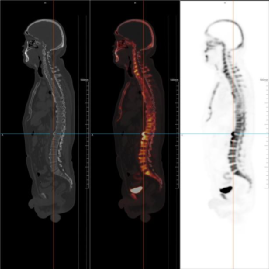

18F-NaF PET/CT骨扫描作为当前骨骼系统疾病诊断的前沿技术,较传统骨扫描具有显著优势。

其核心原理是采用18F-氟化钠(NaF)作为显像剂,该显像剂能与骨骼中的羟基磷灰石快速结合,被骨骼代谢活跃区域特异性摄取。

相较于传统骨扫描,它的灵敏度更高,可提前3-6个月发现骨骼早期病变;图像分辨率更强,能清晰呈现病变的位置、范围、形态及代谢活性;诊断准确性也大幅提升,有效减少漏诊、误诊情况。

该技术可广泛应用于骨转移瘤的早期筛查与分期、原发性骨肿瘤、隐匿性骨折、关节置换后、骨髓炎等诊断与疗效评估、骨质疏松症的精准检测及复杂病因的鉴别,为临床提供全面、可靠的诊断参考。